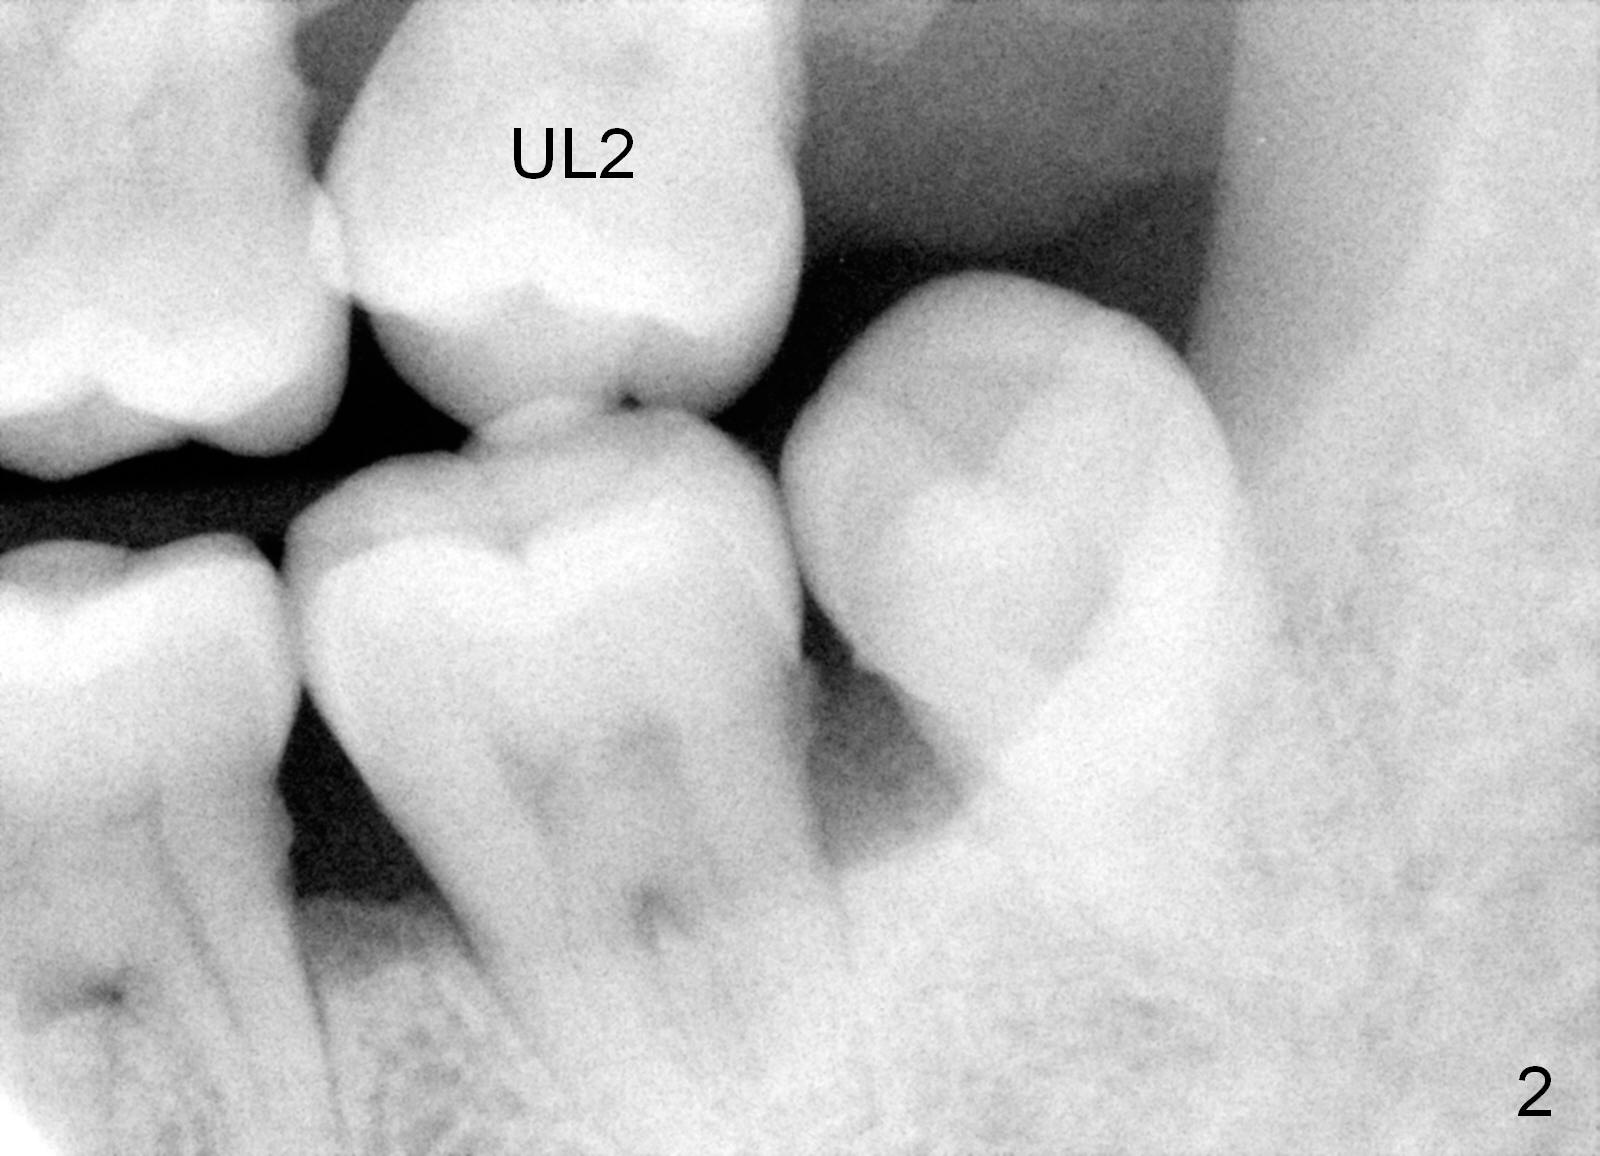

A 49-year-old lady is scared of dentistry. She presented with chronic periodontitis 7 years ago. The lower right 2nd molar had been missing (Fig.1 LR2), while the upper right 2nd molar shifted distally (arrow). Her chief complaint was mobility of #15 (Fig.2,4 UL2 with severe bone loss (*)). The tooth was extracted with expectation of return for implant placement in 6-8 weeks.